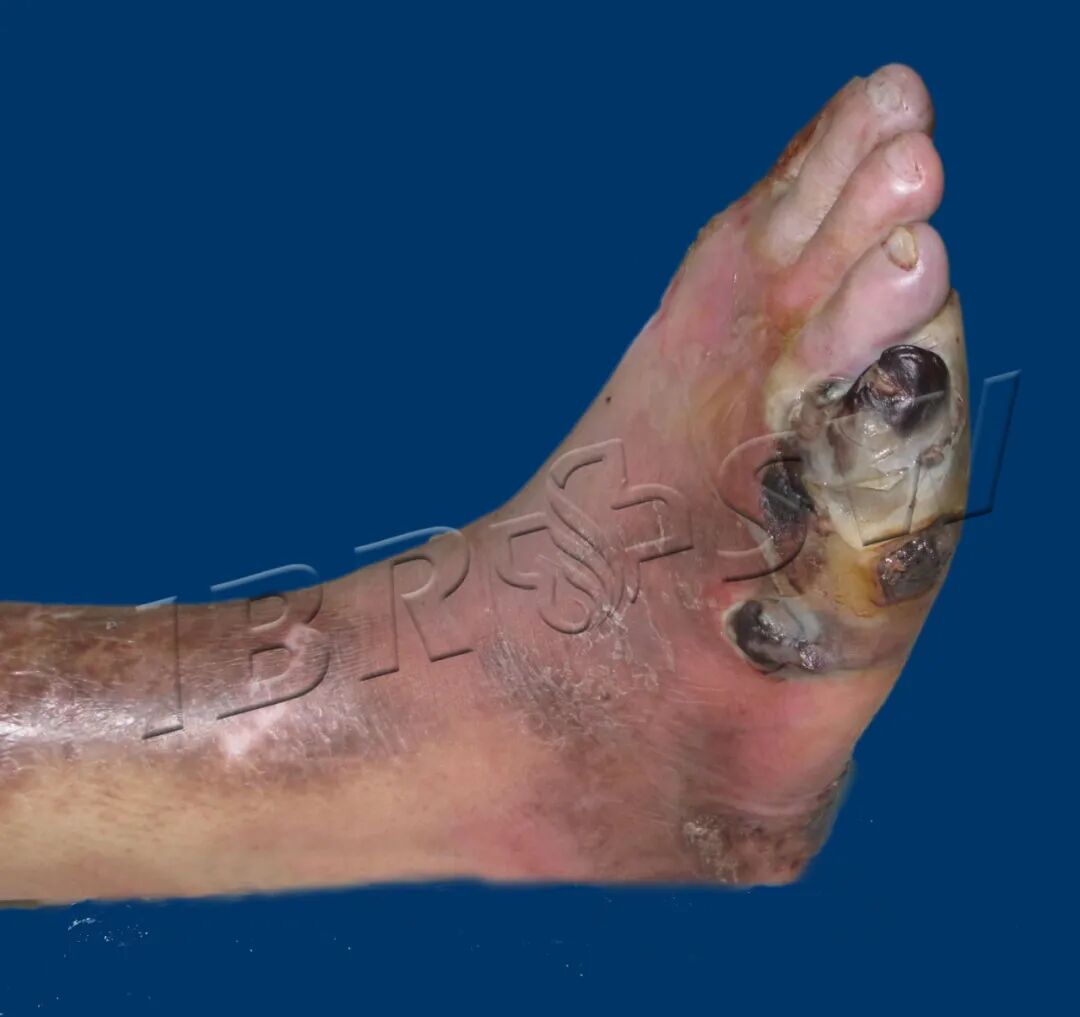

我科收治的糖尿病足患者入院时足部创面情况